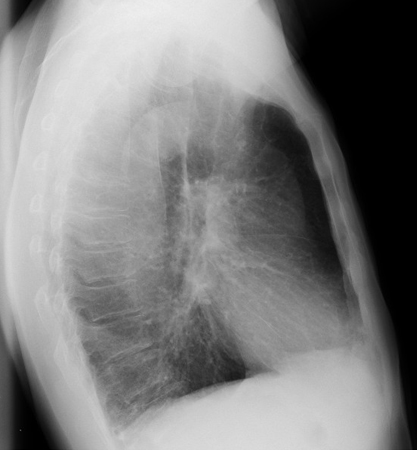

გულმკერდის რენტგენოლოგიური კვლევით

ტესტი

იშვიათადაა დიაგნოსტიკური, მაგრამ სასარგებლოა სხვა პათოლოგიების გამორიცხვისა და მნიშვნელოვანი თანმხლები დაავადებების არსებობის (მაგ., ფილტვის ფიბროზის, კარდიომეგალიის) შესაფასებლად.[1]

შეიძლება გამოვლინდეს ანტეროპოსტერიორული (წინარეუკანა) თანაფარდობის და ფილტვის გამჭირვალობის ზრდა, დიაფრაგმის გადასწორება, ნეკნთაშუა სივრცეების გაფართოება.[Figure caption and citation for the preceding image starts]: ფილტვის ქრონიკული ობსტრუქციული დაავადების (COPD) მქონე პაციენტის გულ-მკერდის რენტგენოგრამა:Manoochehr Abadian Sharifabad, MD -ის კოლექციიდან [Citation ends].

[Figure caption and citation for the preceding image starts]: COPD-ის დროს გულმკერდის რენტგენოგრაფია(გვერდითი პროექცია): გადაბერილი ფილტვები, დიაფრაგმის გადასწორება, ნეკნთაშუა სივრცეების გაფართოება ლატერალურ ჭრილში.Manoochehr Abadian Sharifabad, MD -ის კოლექციიდან [Citation ends].

ასევე შეიძლება გამოავლინიოს COPD-ის ისეთი გართულებები, როგორიცაა პნევმონია ან პნევმოთორაქსი.

შედეგი

გადაბერვა